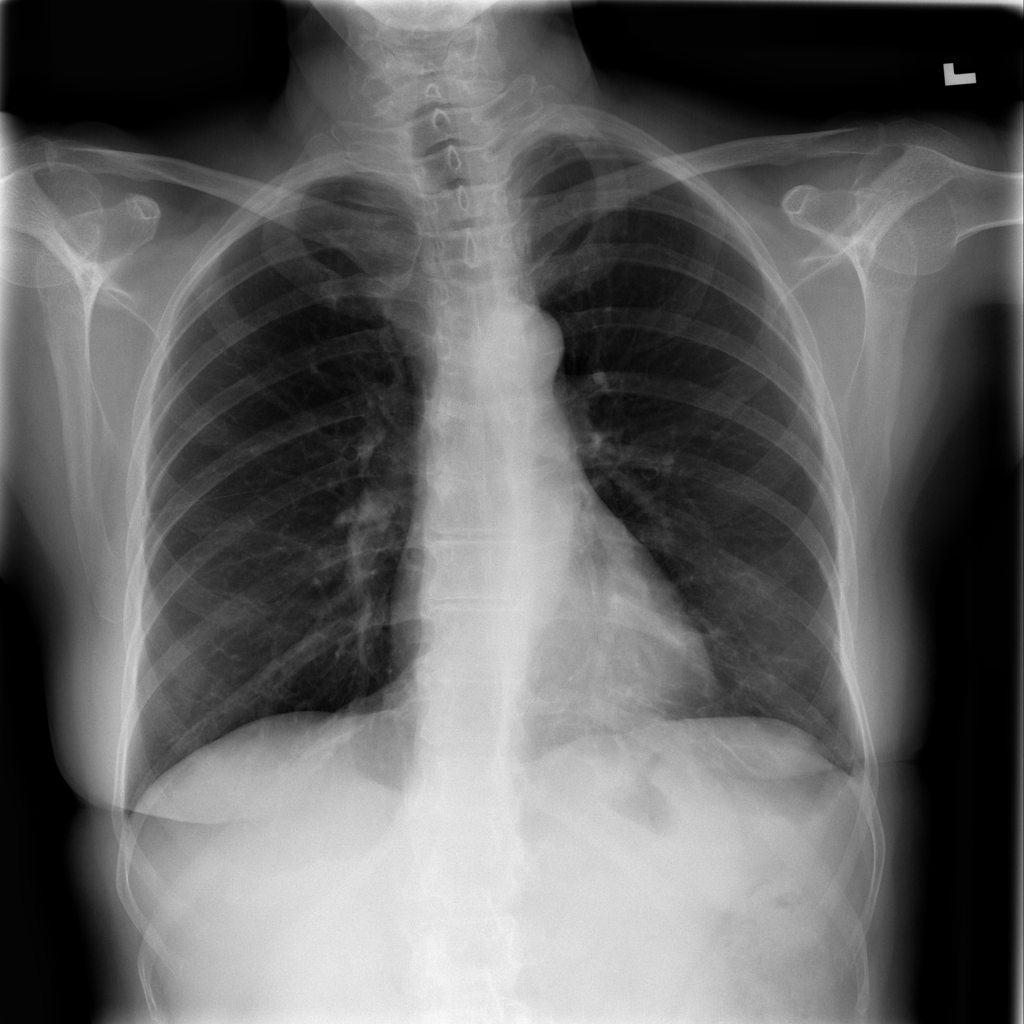

Showing up to 90 reference images for Pneumonia.

PAT-A1E2 · IMG-001Pneumonia

PAT-A1E2 · IMG-001

AP